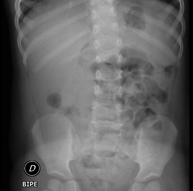

- Abdomen i pelvis

- RX Abdomen

Tècnica que usa els raigs X a través de la qual s'obtenen imatges de l'abdomen (estómac, intestí prim, intestí gros, fetge, ronyons, bufeta, pelvis òssia, etc.) per al seu estudi. - RX Columna lumbar